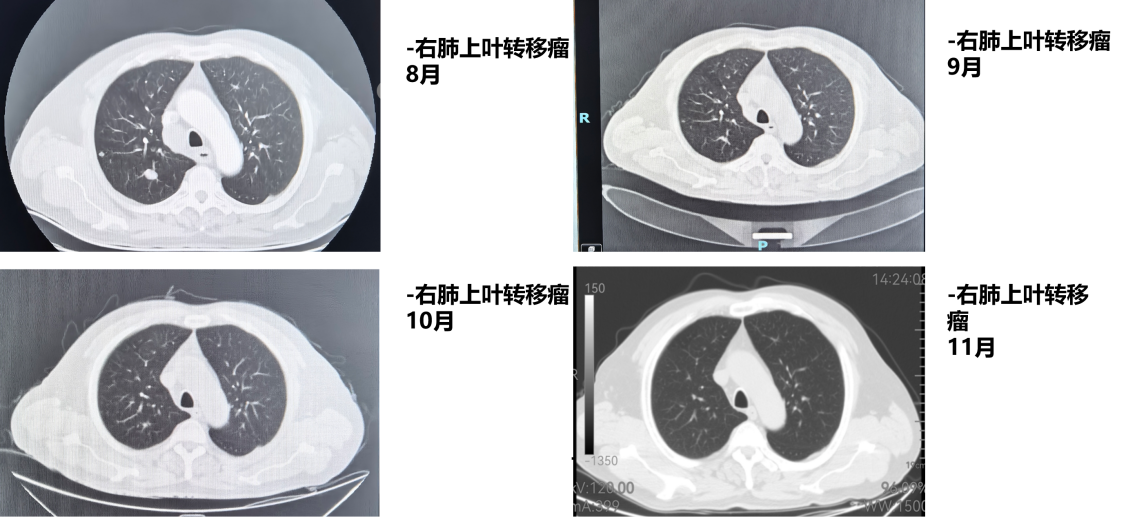

1周期后(2025年9月)复查CT:食管病变、纵隔淋巴结较前减小,双肺转移结节较前部分减小。1周期即显现疗效。

4周期后(2025年11月)复查CT:与2025-10-17日图像对比,食管癌治疗后改变,同前相仿;纵隔淋巴结治疗后改变,较前减小;双肺多发小结节,考虑转移瘤治疗后改变,部分较前略减小。

疗效评估:达到部分缓解(PR)

本例患者PD-L1 CPS评分为3分,属于CheckMate 648研究中获益更为显著的PD-L1阳性人群。经过4个周期纳武利尤单抗联合化疗后,影像学复查显示原发灶及所有转移病灶均明显缩小,疗效评估达PR,与研究中PD-L1阳性患者高达53%的ORR相符。